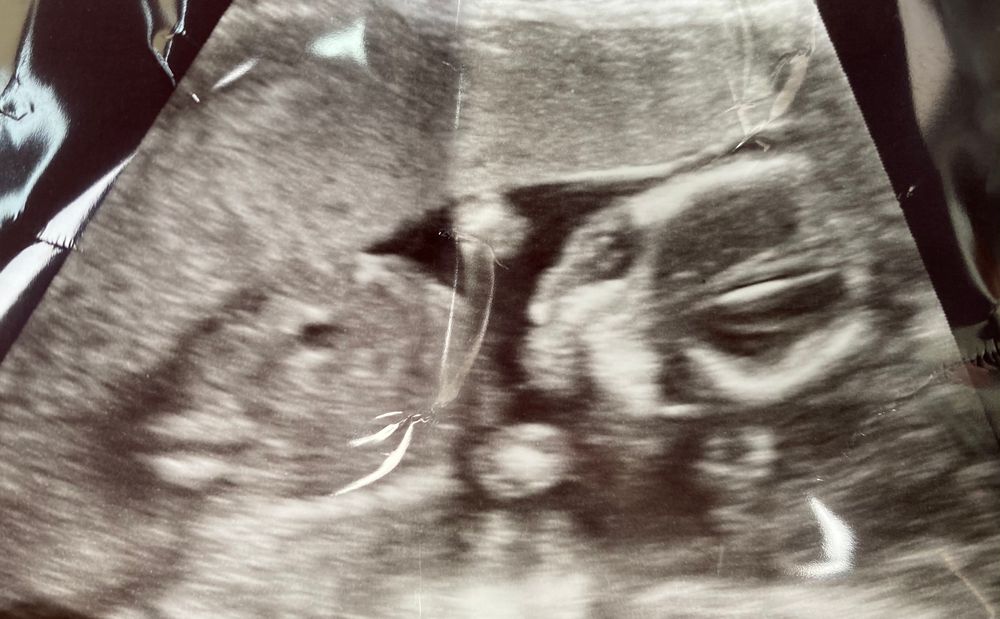

16+6

И у нас на 60 % девочка,ножки скрестила ,врач не уверена ,но несколько раз ножки поднимала и ничего там не было🤷♀️😅

Вес-176 грамм, сказали норма, но вроде немного больше? У кого как было?

плацента по передней стенке, поэтому ещё не чувствую шевелений.

Через недельку ещё к своему врачу, думаю девочку подтвердит.

Вот такие мы уже😍